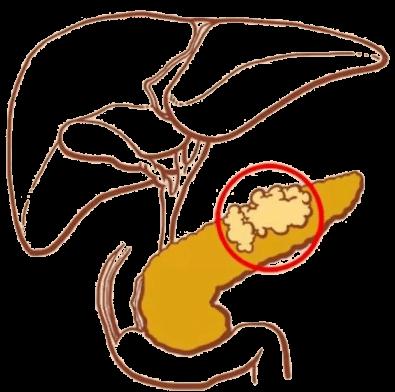

肝脏可以通过分泌胆汁促进消化,而胆囊是储存胆汁的部位,摄入食物后胆汁就会从胆囊中释放进入肠道,帮助分解脂肪,胰腺则通过分泌各种胰酶和胰液来促进食物的分解及吸收。

由于胆管和胰管共同开口于十二指肠降部的主乳头部,如此处梗阻,不仅可导致胆汁返流入胰管,还可导致壶腹部功能障碍,导致肠液返流入胰管。因胆汁为碱性,胰液中的消化酶在碱性环境下容易被激活,导致多种胰酶的酶原在胰腺导管和腺泡内被提前激活,产生胰腺的自我消化,从而导致胰腺自身消化的化学性炎症,导致急性胰腺炎。

胰腺为什么会自己"消化"自己?

以胆源性胰腺炎为例,胆囊结石或胆管结石,在胆道移行的过程,引起胆管梗阻,胆汁淤积,不仅可引起梗阻性黄疸和急性胆管炎,如结石堵塞胆胰管结合部,即胆胰管共周开口的十二指肠主乳头的壶腹部,导致壶腹部功能障碍,胆汁或十二指肠液返流入胰管,由于胆汁是碱性、肠液中含有肠激酶等可激活胰液中的胰蛋白酶原,导致胰蛋白酶在胰腺中提前激活,胰蛋白酶除可自身激活外,还可激活糜蛋白酶等多种消化酶,导致胰腺腺泡中的胰原颗粒中的各种酶原被提前激活,此为酶原在胰腺腺泡中激活的级联反应,多种消化酶在胰腺腺泡内激活后,会自身消化胰腺组织,就是所说一发狠可是会把自己"吃掉"的!